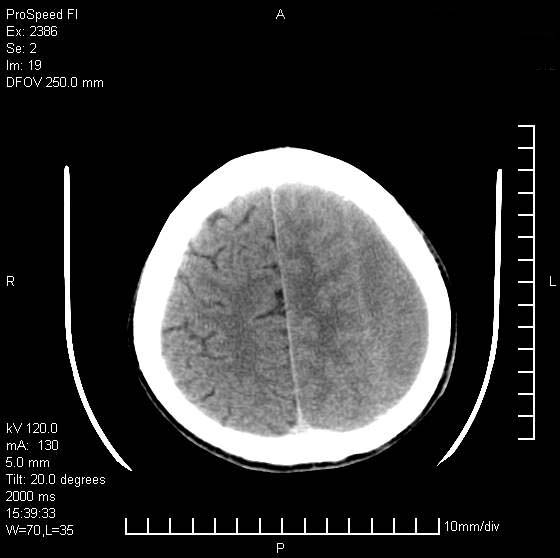

以下是引用天南地北在2007-9-19 18:43:00的发言:[br]典型慢性硬膜外血肿[br][br][本贴已被 天南地北 于 2007-9-19 18:44:11 修改过]

以下是引用曼一拍在2007-9-20 11:06:00的发言:[br]支持慢性硬膜下血肿.[br]慢性硬膜下积液:血肿有包膜,ct值稍高于脑脊液,增强可有染色。不典型者血肿可多呈梭形.是硬脑膜与蛛网膜之间的潜在腔隙内的血肿。[br]鉴别:[br]1\\硬膜外血肿:是颅脑外伤后脑膜或板障内血管破裂,血液在颅骨与硬膜之间积聚所致.通常是脑膜动脉破裂,也可因静脉窦破裂或颅骨的板障静脉出血,发生于外伤的着力部,常与颅骨骨折并存。脑膜动脉出血则急,若是板障静脉出血在则可有慢性。[br]2\\硬膜下积液:(硬膜下水瘤)[br]是由于蛛网膜破裂,脑脊液经蛛网膜破口进入硬膜下腔不能回流。或水肿阻塞而形成。[br]ct表现:颅骨内板下方新月形低密度区近似脑脊液密度;占位效应清,周围无脑水肿。[br]